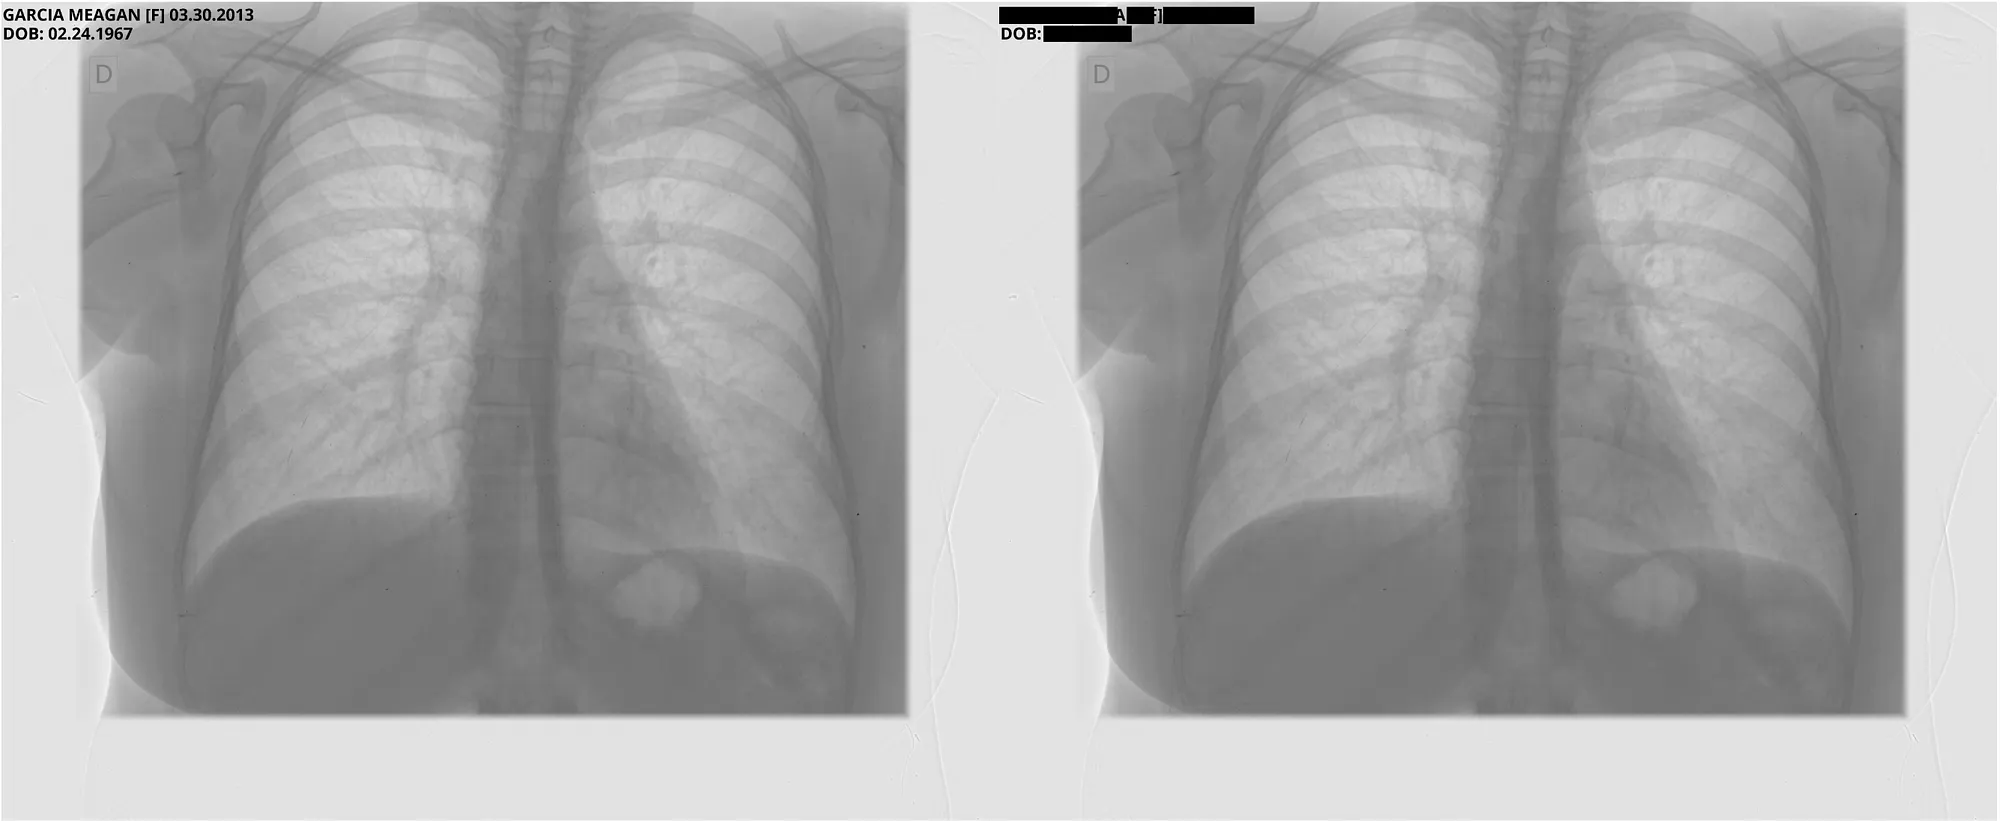

Pixel DeIdentification Original ( Left ) -> DeIdentified ( Right )

Reference : MIDI-B Pixel Metadata DeIdentification Notebook